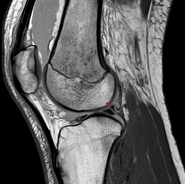

Posterior meniscofemoral ligament on MRI, coronal

Posterior meniscofemoral ligament (Wrisberg) behind the posterior horn of the lateral meniscus close to its insertion. Sometimes wrongly interpreted as a meniscal tear.